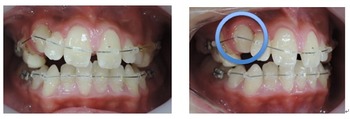

以下の上顎の症例では左右の第一小臼歯を抜かないと治療出来ないと説明があるはずです。しかし、当院での治療終了時には顎骨が拡大して綺麗に歯が並んでいます。

初診時 終了時

当院では拡大装置などを使用する事無く歯並びを綺麗に並べることが出来ます。

出来るだけ見えにくい矯正装置(ブラケット)を上下顎に装着して歯並びを整えていきます。矯正装置を装着後3日から7日ぐらいまでの間は歯が動きだすために軽い痛みを感じることがあります。

次にMEAW(マルチループ)を利用する事で咬み合わせの高さや前歯の傾斜を整えていきます。

また、MEAW(マルチループ)はゴムを24時間使用する事で最大の効果を発揮することが出来ます。

当院では簡易なMEAW(マルチループ)を使用する事で上下の前歯部をより綺麗な歯並びにしていきます。

この時にも24時間使用するゴムが大切です。

治療期間3年0か月で機能的で美しい咬み合わせが完成しました。

今回の症例は一般的に抜歯(第一小臼歯)が必要な症例ですが当院では非抜歯で治療する事が出来ました。